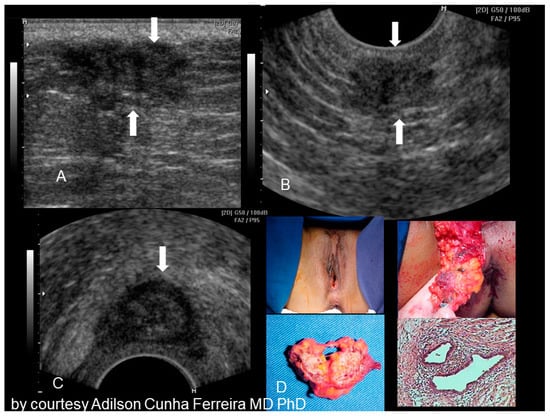

2.6. Perineal Endometriosis

Endometriosis of the perineum and vulva is extremely rare, with the most common site being episiotomy scars. Color Doppler ultrasound revealed a subcutaneous nodule with an irregular outline and echo-complex density underlying the episiotomy scar [23]. Episiotomy scar endometriosis represents the less frequent type of scar endometriosis with a much lower prevalence compared to endometriosis in abdominal wall scars [9]. The typical ultrasonographic finding associated with perineal endometriosis is the presence of a solid lesion near to the episiotomy scar (Figure 11).

Figure 11. Sonographic features of perineal endometriosis (see white arrow) (AC). The visual appearance, the specimen, and the pathology picture (D) (courtesy of Adilson Cunha Ferreira, MD, PhD).